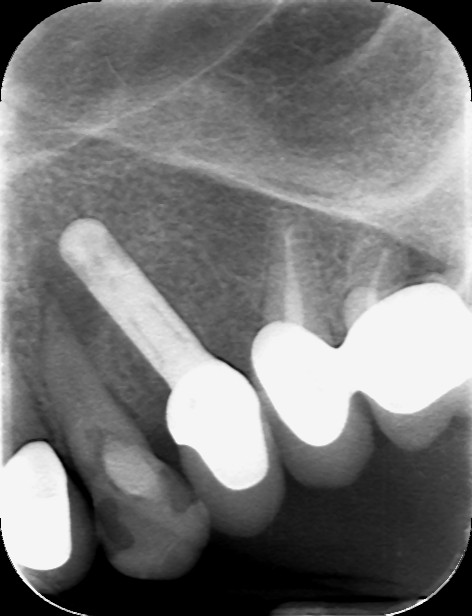

Stamattina mi è capitata sott'occhi questa OPT, da cui si evince che gli impianti inferiori di destra sono perfettamente collocati e alloggiati nell'osso, mentre in alto a sinistra si vede un impianto in 24 invadere lo spazio parodontale del 23 e determinarne una estesa lesione periapicale.

Sezione tomografica in 45: L’impianto in 45, che sembrava perfettamente collocato, è invece esposto per più della metà della sua lunghezza.